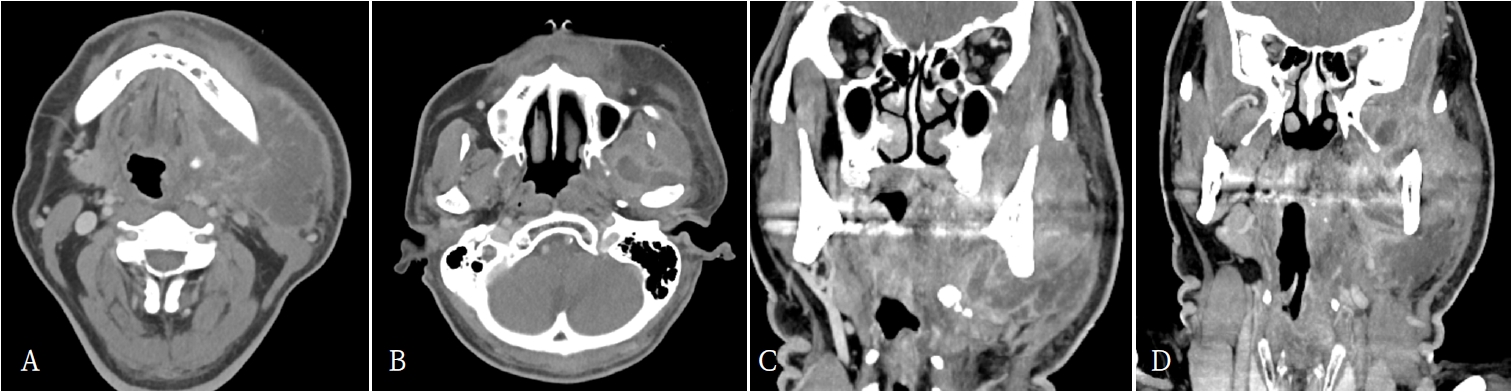

62세 남환이 3일 전부터 발생한 좌측 안면 종창과 입술 감각 저하를 주소로 본원 응급실에 내원하였다. 기저질환으로 당뇨병이 있었으며, 과거력에서 우측 하지에 발생한 괴사성 근막염으로 절개 및 배농술, 광배근 유리피판술을 수술받은 병력이 있었다. 내원 당시 좌측 하악각(mandibular angle)에서 악하(submandibular area)부위에 이르는 종창과 발적이 관찰되었다. 활력징후는 혈압 135/82 mmHg, 맥박수 122회/분, 호흡수 20회/분, 체온 37.8℃, 산소포화도 99%였다. 혈액검사에서는 백혈구 20.0 ×10³/μL, 호중구 84.5%(정상 40~75%), ESR 88 mm/hr(정상 0~10 mm/hr), CRP 270 mg/L(정상 0~5 mg/L)로 확인되었다. 조영증강 경부 전산화단층촬영(computed tomography; CT)에서는 좌측 악하부, 내·외측 익돌하악부(pterygomandibular space), 교근 및 인두주위(massteric and parapharyngeal space) 공간에 농양 소견이 관찰되었다(Fig. 1).

Contrast-enhanced neck computed tomographic images reveal abscess formation in the left submandibular space, pterygoid space (both medial and lateral), masseteric space, and parapharyngeal space. A and B. axial views, C and D. coronal views